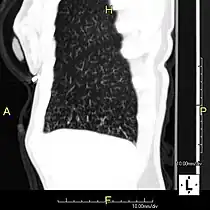

- Oblique sagittal CT image showing lower lobe cylindrical bronchiectasis